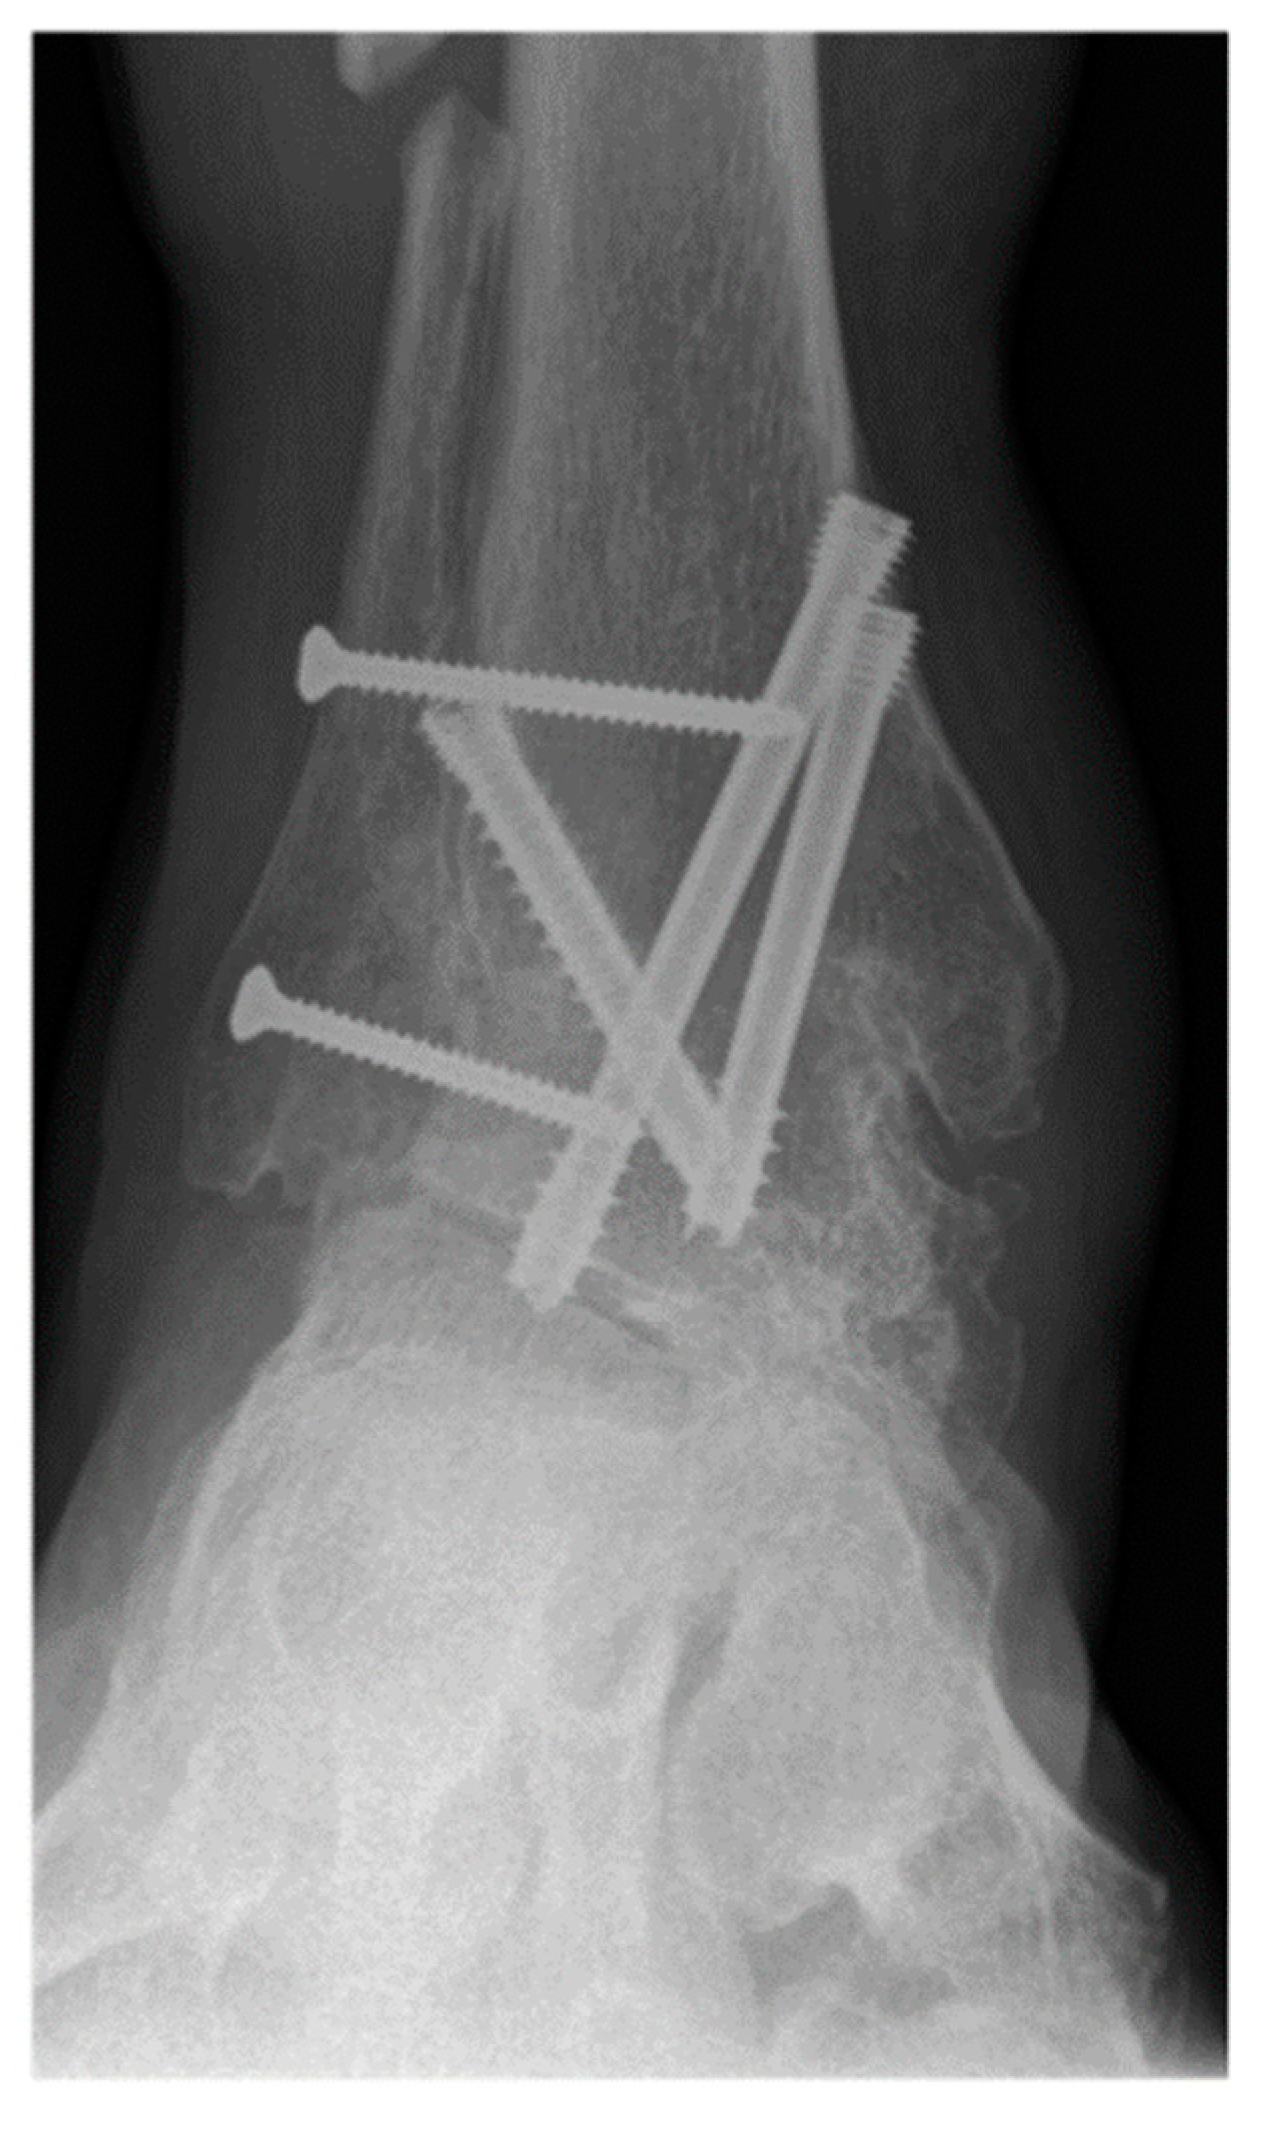

Figure 1.

A 57-year-old male patient presenting end-stage varus tibiotalar osteoarthritis.